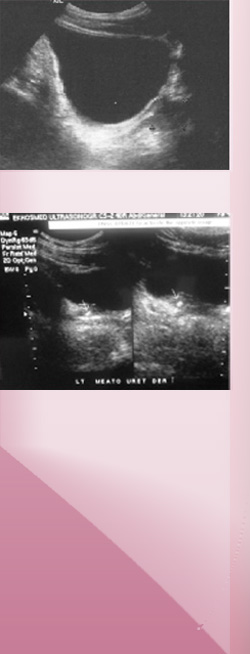

Ecografía pélvica masculina

Evaluación de vejiga

y próstata.